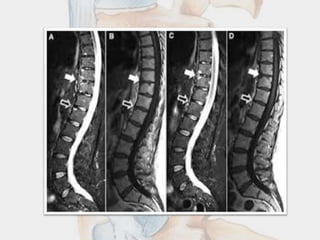

LUMBAR SPINE SHOWS

• Squarring of verttebrae

• Loss of lumbar lordosis.

• Bridging osteophytes

• Bamboo spine

LUMBAR SPINE SHOWS •Squarring of verttebrae • Loss of lumbar lordosis. • Bridging osteophytes • Bamboo spine